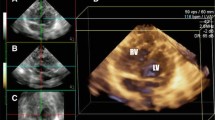

The 4D RV-FUNCTION 2.0 software is a semi-automated program that requires the operator’s input in the initial steps to identify certain landmarks and later in the process for contour adjustments. Initially, the system will slice the full volume and automatically generate five end-diastolic 2D frames of the ventricles: three are used to identify and mark the LV and two for the RV. Sequentially, a short-axis cut at mid ventricular level is automatically developed (Fig. 1). The operator initially identifies the LV apex and mitral valve in each 4 and 2 chamber views. On the remaining two longitudinal frames, the mid TV and the RV apex are marked. Finally, the operator places 2 landmarks corresponding to the aortic valve hinge points (AV1–2) on the LV apical long-axis view (Fig. 1). When this step is completed a short-axis cut at the mid ventricular level is generated. On this image, the anterior (AJL) and posterior junction (PJL) of the RV free wall with the interventricular septum are identified and marked. Finally, the septum-to-RV free wall distance at mid ventricular level is set. This will conclude the alignment of the 3D image.

Operator identifies the LV apex and mitral valve in the 4 and 2 chamber views of the LV and the TV and the RV apex in the remaining two longitudinal frames of the RV. On the LV apical 3-chamber view, the operator places two landmarks corresponding to the aortic valve hinge points (AV1–2). In the last short-axis view two points are placed on the anterior and posterior junctions between the septum and the free wall of RV. AJ anterior junction, AV aortic valve, Ch chamber, LV left ventricle, PJ posterior junction, RV right ventricle, SAX short axis, TV tricuspid valve

The software, using reflected speckles, automatically traces the boundaries of the RV in the longitudinal 4-chamber view at end diastole and end systole and in three corresponding short-axis cuts at preset levels of the RV. Following automated tracing of the endocardium by the system, additional manual adjustments are feasible. Whenever, the final adjustments are approved by the operator, the RV endocardial surface is automatically traced over the entire cardiac cycle and values of RV diastolic, systolic, and stroke volumes in addition to EF are provided (Fig. 2). The change in RV volumes over time is depicted as a dynamic 3D cast (Fig. 3).

RV endocardial surface is automatically traced over the entire cardiac cycle and is depicted in 3 short and one 4-chamber cuts, both in diastole and systole. Values of RV diastolic, systolic, and stroke volumes and EF are provided. Adjustments in every image and frame are feasible. EDV end-diastolic volume, EF ejection fraction, ESV end-systolic volume, Ch chamber, RV right ventricle, SAX short axis, SV stroke volume